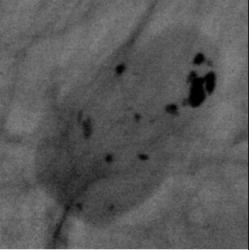

Протокол исследования. В верхнем наружном квадранте инволютивно измененной молочной железы (в годы климакса) определяется тень значительных размеров, овальной формы, средней интенсивности, неоднородной структуры с довольно ровными контурами – фиброаденома. На фоне тени фиброаденомы определяются полиморфные и различные по величине известковые включения. В параареолярной области определяется тень круглой формы средней интенсивности, однородной структуры с ровными контурами – мелкая фиброаденома. Представленные снимки во вложенных файлах (см. ниже). 1 – снимок в прямой проекции; 2 – снимок в боковой проекции; 3, 4 – участки с патологическим образованием, выделенные «навигатором» для более детального анализа. 5- «кальцинат», выделенный навигатором – структура кальцината неоднородная.

Заключение: Инволютивная молочная железы в годы климакса. Фиброаденома крупных размеров левой молочной железы с локализацией в верхнем наружном квадранте с известковыми включениями. Фиброаденома в параареолярной области.